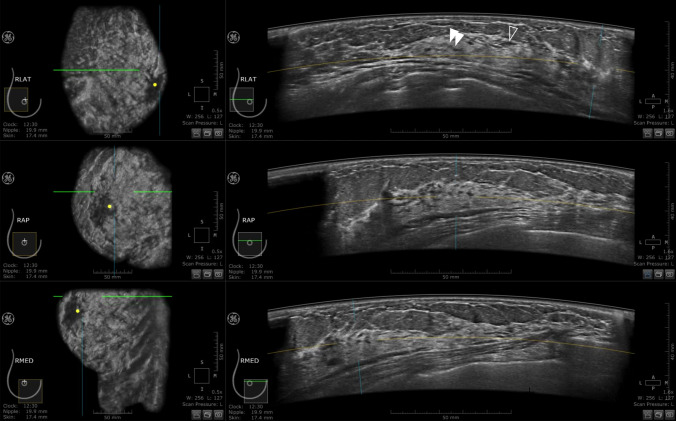

Fig. 2.

Right breast ABUS images of a 35-year-old woman at 5 weeks 2 days of pregnancy. Lateral (LAT), anteroposterior (AP), and medial (MED) images from top to bottom, with a coronal section presented on the left and a horizontal section on the right. The open arrowhead indicates a ductal image, but it was not sufficiently developed to be considered indicative of the gestational period. Neither criterion 1 nor 2 was met in this case. In addition, the double arrowhead shows an anechoic duct-like structure, which was not determined to be a milk duct but likely corresponded to the stroma supporting the ducts